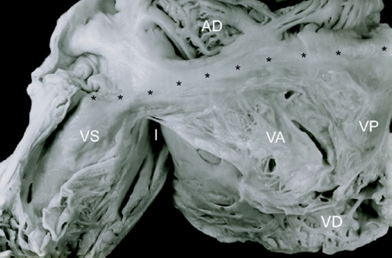

La doble entrada ventricular es un tipo de conexión auriculoventricular univentricular en la que ambas aurículas se abren a un solo ventrículo y presenta 3 modalidades: en ventrículo izquierdo5, en ventrículo derecho6 y en ventrículo único a través de 2 válvulas auriculoventriculares o de una válvula auriculoventricular común7,8 (Figs. 2 y 3).

Figura 2 Esquemas que muestran el concepto de conexión auriculoventricular univentricular que comprende 2 tipos de conexión: doble entrada y ausencia de conexión en sus respectivas modalidades. VD: ventrículo derecho; VI: ventrículo izquierdo; VU: ventrículo único.

Con relación al ventrículo único ha existido una variada nomenclatura lo que ha propiciado múltiples controversias; en la mayoría de las sistematizaciones se acuñó el término de ventrículo único para denominar corazones con estructura biventricular lo que constituyó una contradicción11–13, por ello se prefirió describir morfológicamente esos corazones, por ejemplo el ventrículo único izquierdo correspondió a la doble entrada en ventrículo izquierdo, el ventrículo único de tipo derecho fue equivalente a la doble entrada en ventrículo derecho y el ventrículo único de tipo indeterminado correspondió al verdadero corazón univentricular como los especímenes de este estudio. Para determinar la naturaleza de estas malformaciones cardíacas Anderson et al.7,8 propusieron el concepto de conexión auriculoventricular univentricular en la que como su nombre indica un solo ventrículo recibe la o las conexiones auriculoventriculares y aquí se incluyó además de la doble entrada ventricular la ausencia de conexión auriculoventricular (Fig. 2).